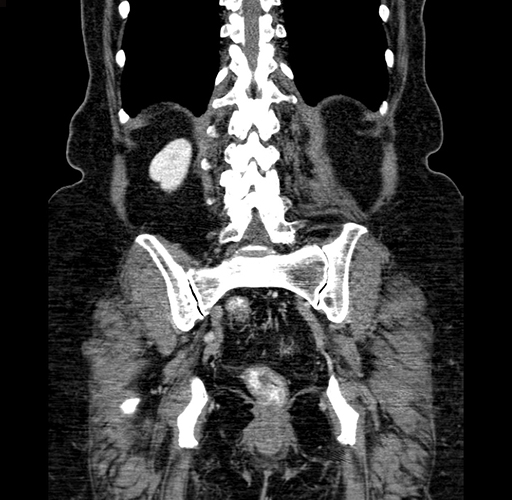

Coronal Venous